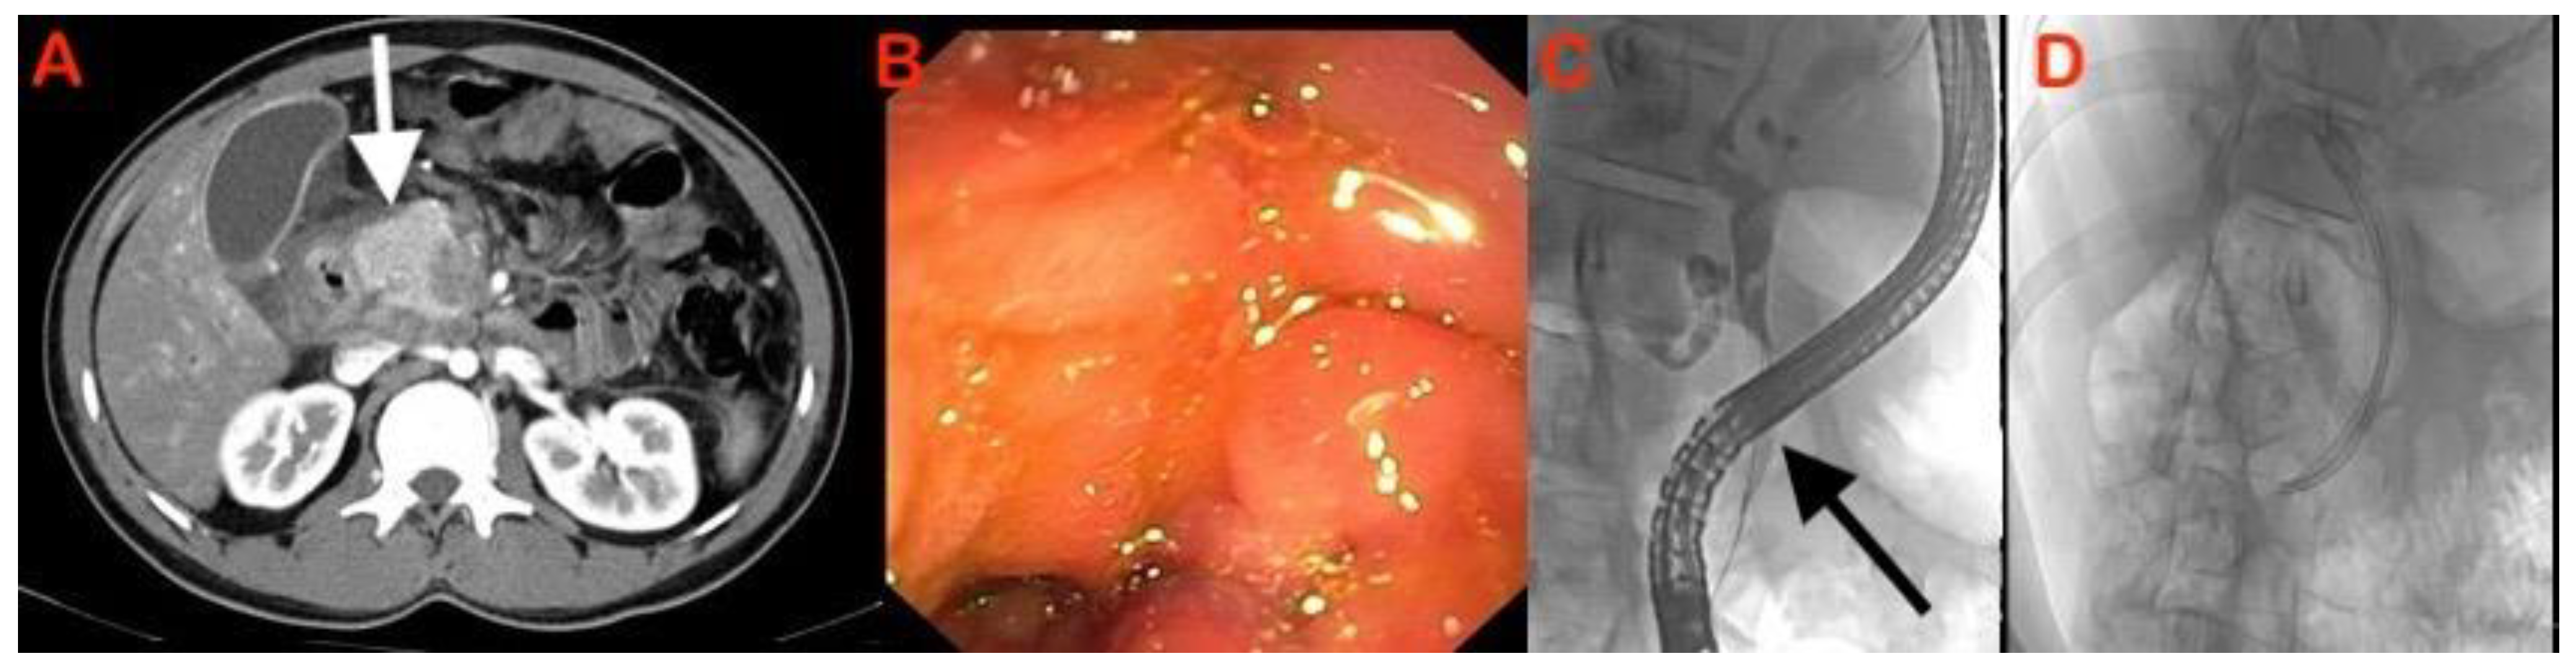

7.2. Autoimmune Pancreatitis

- Lee, L.K.; Sahani, D.V. Autoimmune pancreatitis in the context of IgG4-related disease: Review of imaging findings. World J. Gastroenterol. 2014, 20, 15177–15189. [Google Scholar] [CrossRef]

- Shimosegawa, T.; Chari, S.T.; Frulloni, L.; Kamisawa, T.; Kawa, S.; Mino-Kenudson, M.; Kim, M.H.; Klöppel, G.; Lerch, M.M.; Löhr, M.; et al. International Consensus Diagnostic Criteria for Autoimmune Pancreatitis: Guidelines of the International Association of Pancreatology. Pancreas 2011, 40, 352–358. [Google Scholar] [CrossRef]

- Ichikawa, T.; Sou, H.; Araki, T.; Arbab, A.S.; Yoshikawa, T.; Ishigame, K.; Haradome, H.; Hachiya, J. Duct-penetrating sign at MRCP: Usefulness for differentiating inflammatory pancreatic mass from pancreatic carcinomas. Radiology 2001, 221, 107–116. [Google Scholar] [CrossRef] [PubMed]

- Manfredi, R.; Frulloni, L.; Mantovani, W.; Bonatti, M.; Graziani, R.; Pozzi Mucelli, R. Autoimmune pancreatitis: Pancreatic and extrapancreatic MR imaging-MR cholangiopancreatography findings at diagnosis, after steroid therapy, and at recurrence. Radiology 2011, 260, 428–436. [Google Scholar] [CrossRef] [PubMed]

- Hoki, N.; Mizuno, N.; Sawaki, A.; Tajika, M.; Takayama, R.; Shimizu, Y.; Bhatia, V.; Yamao, K. Diagnosis of autoimmune pancreatitis using endoscopic ultrasonography. J. Gastroenterol. 2009, 44, 154–159. [Google Scholar] [CrossRef] [PubMed]

- Okabe, Y.; Ishida, Y.; Kaji, R.; Sugiyama, G.; Yasumoto, M.; Naito, Y.; Toyonaga, A.; Tsuruta, O.; Sata, M. Endoscopic ultrasonographic study of autoimmune pancreatitis and the effect of steroid therapy. J. Hepatobiliary Pancreat. Sci. 2012, 19, 266–273. [Google Scholar] [CrossRef]